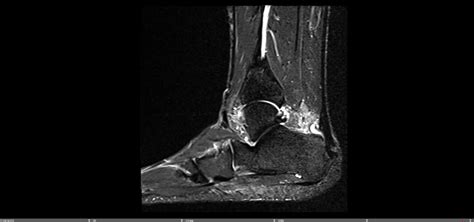

To confirm the diagnosis and rule out other potential issues, your doctor might order imaging tests. X-rays are often the first line of imaging. They’re great for visualizing bone spurs, which are common with insertional Achilles tendonitis, and can help rule out fractures or other bone abnormalities. If more detail is needed, they might recommend an ultrasound or an MRI . An ultrasound can provide real-time images of the tendon, showing inflammation, degeneration, or tears. An MRI offers a more detailed view of soft tissues, allowing the doctor to assess the extent of tendon damage and identify any other soft tissue problems in the area.